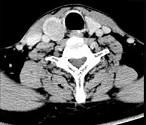

问题 男,43岁,因右颈部扪及一包块来院就诊。如图所示该患者应诊断为()

选项 A.甲状腺腺瘤 B.甲状腺腺癌 C.结节性甲状腺肿 D.甲状腺原发淋巴瘤 E.甲状腺转移瘤

答案 A